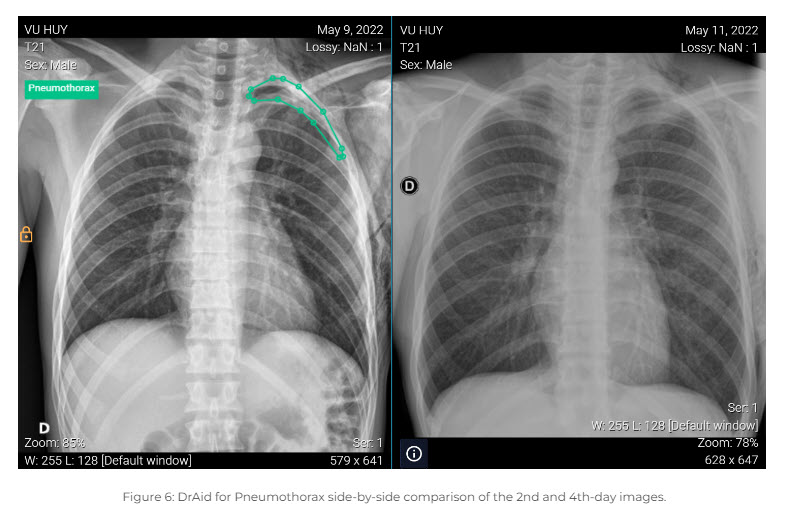

ได้รับทุนสนับสนุนจาก Vingroup ซึ่งเป็นหนึ่งในบริษัทมหาชนที่ใหญ่ที่สุดของเวียดนาม VinBrain เป็นผู้สร้าง DrAid ซึ่งเป็นซอฟต์แวร์ AI เพียงตัวเดียวสำหรับการวินิจฉัยเอกซเรย์อัตโนมัติในเอเชียตะวันออกเฉียงใต้ และเป็นหนึ่งในแพลตฟอร์ม AI แรก ๆ ที่องค์การอาหารและยา (FDA) ให้การรับรองในการตรวจจับคุณลักษณะที่ชี้นำ ของอาการปอดแฟบจากการเอกซเรย์ทรวงอก

DrAid ได้รับการฝึกฝนจากชุดข้อมูลมากกว่า 2.5 ล้านภาพในโรงพยาบาลมากกว่า 100 แห่งในเวียดนาม เมียนมาร์ นิวซีแลนด์ และสหรัฐอเมริกา ซอฟต์แวร์นี้ใช้การวิเคราะห์ AI กับภาพทางการแพทย์สำหรับผู้ป่วยมากกว่า 120,000 รายในแต่ละเดือน VinBrain ยังสร้างโฮสต์ของแอปพลิเคชัน AI อื่น ๆ รวมถึงผลิตภัณฑ์ telehealth ที่วิเคราะห์ผลการทดสอบในห้องปฏิบัติการ รายงานทางการแพทย์ และบันทึกสุขภาพอิเล็กทรอนิกส์อื่น ๆ